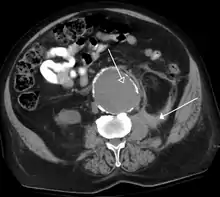

A CT scan image showing a ruptured abdominal aortic aneurysm.

Computed tomography of the abdomen and pelvis is an application of computed tomography (CT) and is a sensitive method for diagnosis of abdominal diseases. It is used frequently to determine stage of cancer and to follow progress. It is also a useful test to investigate acute abdominal pain (especially of the lower quadrants, whereas ultrasound is the preferred first line investigation for right upper quadrant pain). Renal stones, appendicitis, pancreatitis, diverticulitis, abdominal aortic aneurysm, and bowel obstruction are conditions that are readily diagnosed and assessed with CT. CT is also the first line for detecting solid organ injury after trauma.